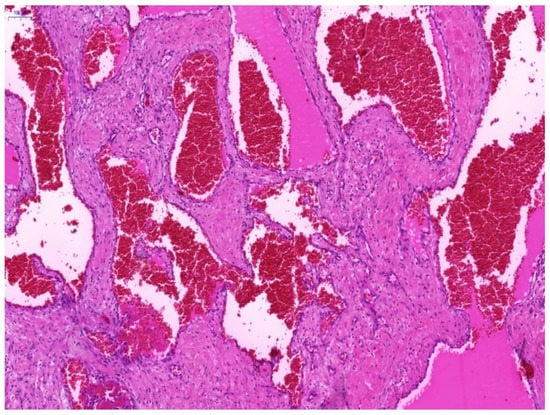

3. Results